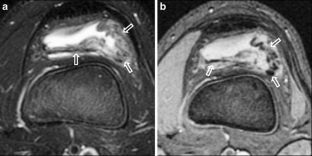

MR findings of synovial disease in children and young adults: Part 1

Synovial diseases in children can be classified into normal structures as potential sources of pathology (synovial folds: plicae, infrapatellar fat pad clefts); noninfectious synovial proliferation (juvenile idiopathic arthritis, hemophilic arthropathy, lipoma arborescens, synovial osteochondromatosis, pigmented villonodular synovitis, reactive synovitis), and infectious synovial proliferation, deposition disease, vascular malformations, malignancy (including metastasis) and intra-articular/periarticular cysts and cyst-like structures (ganglia). Familiarity with characteristic MR imaging findings of synovial diseases in children and young adults will enable a more confident diagnosis for earlier intervention and directed therapy. The first part of this paper will cover potential pathology of normal synovial structures as well as noninfectious synovial proliferation.